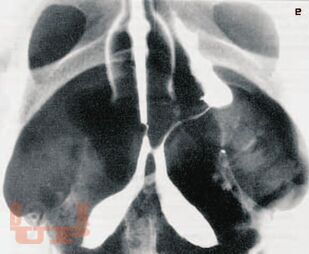

В монографии проанализированы данные литературы и собственные результаты обследования и лечения более 200 пациенток с непроходимостью маточных труб, страдающих бесплодием. Детально описаны методика, рентгенологические и клинические результаты трансцервикальной селективной сальпингографии и реканализации маточных труб под контролем рентгеноскопии. Определена роль чрескатетерных методик в диагностике и лечении трубного бесплодия, их преимущества и недостатки по сравнению с существующими методами коррекции проходимости маточных труб. Сделано заключение о важной роли малоинвазивных трансцервикальных методов в обследовании и лечении пациенток с бесплодием.